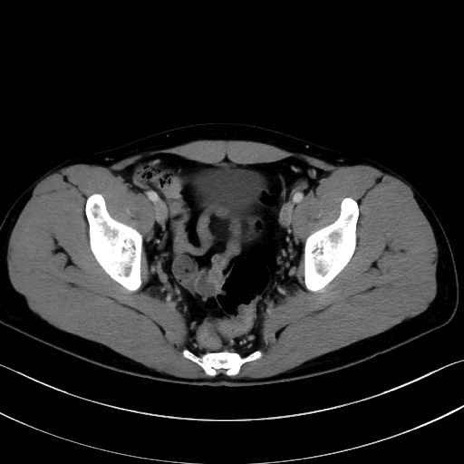

精嚢(seminal vesicle)のCT画像における解剖

症例

【症例】20歳代 男性 スクリーニング